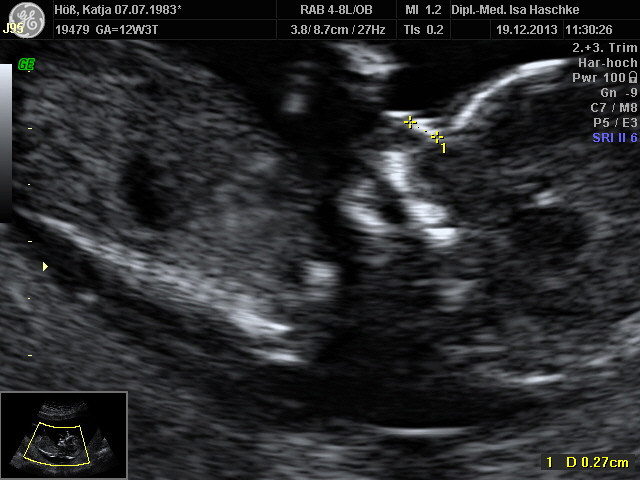

Schwangerschaftswoche 13

Nach unserer Zustimmung und Einverstandnis konnte nun die Nackenfaltenmessung des ungeborenen gemacht werden, am 19.12.2013 wurde diese durchgeführt. Der Befund ist positiv ausgefallen, zu 0,0083 % konnte eine Fehlbildung ausgeschlossen werden, worüber wir sehr glücklich sind.